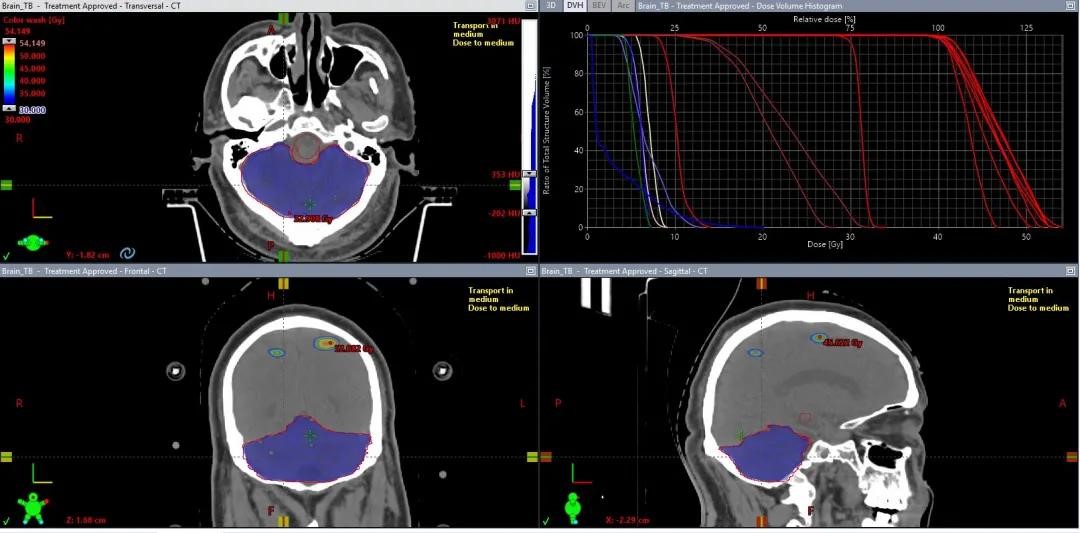

肺癌单发脑转移,40Gy/10F,最大径4.77cm,

跌落到50%处方剂量仅需5mm,CI为1.03

2020年10月28日,首例HyperArc治疗开展,全程共10分钟,其中出束开始到治疗结束不到5分钟。因为治疗的高度自动化,技师无需进入治疗室重新对患者进行摆位或者手动移床,治疗时间远远低于常规非共面治疗。

肺癌脑多发转移,5个靶点,最大直径3cm,48Gy/12F,

CI:1.14、5mm外跌落到50%处方剂量

03 超多发脑转移

67个Mets,39Gy/13F,全脑平均剂量17Gy,

明显低于全脑照射,而且病灶可以给到更高剂量

67个靶点,每个都能达到处方覆盖要求

使用HyperArc一键式完成67个靶点治疗只要10分钟

04 小脑大靶区+大脑7个小靶点

小脑:30Gy/10F,要求剂量均匀

大脑靶点:40Gy/10F,SRS照射

同时满足大脑小靶点SRS照射和小脑均匀照射